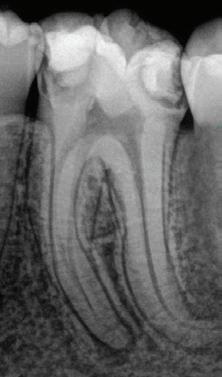

EdgePRO®

Cleaning. Enhanced.

Provides outstanding Cleaning, Debridement and Disinfection by removing infected tissue, biofilm and smear layer killing up to 99% of bacteria commonly found in the root canals. (1,2,3,4) This should give you the confidence you need to treat even the most complex anatomies.

Endodontics. Streamlined.

Lets “You be You”– shape and obturate the canals the way you want without the need to change your technique. EdgePRO™ offers the potential for streamlined workflow and one-visit treatment resulting in reduced treatment time and patient visits.

Technology. Affordable.

Has state-of-the-art technology at more affordable pricing that is as low as 1/3 the cost of other irrigation devices. EdgePRO™ gives your practice access to the future of Endodontics and an edge in winning more referral business.